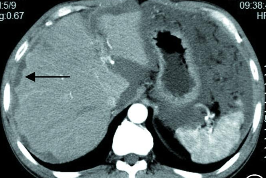

胆管细胞癌为肝脏常见恶性肿瘤,居肝脏原发恶性肿瘤第二位,根据其形态可分为肿块型、管内生长型和管外浸润型。肿块型胆管细胞癌的特征为瘤内含有纤维组织,导致邻近肝包膜牵拉皱缩和增强后延迟性强化的特点。

胆管细胞癌,增强门脉期呈相对低密度,边界不清,邻近肝包膜凹陷。另外病灶周围可见数枚卫星灶。